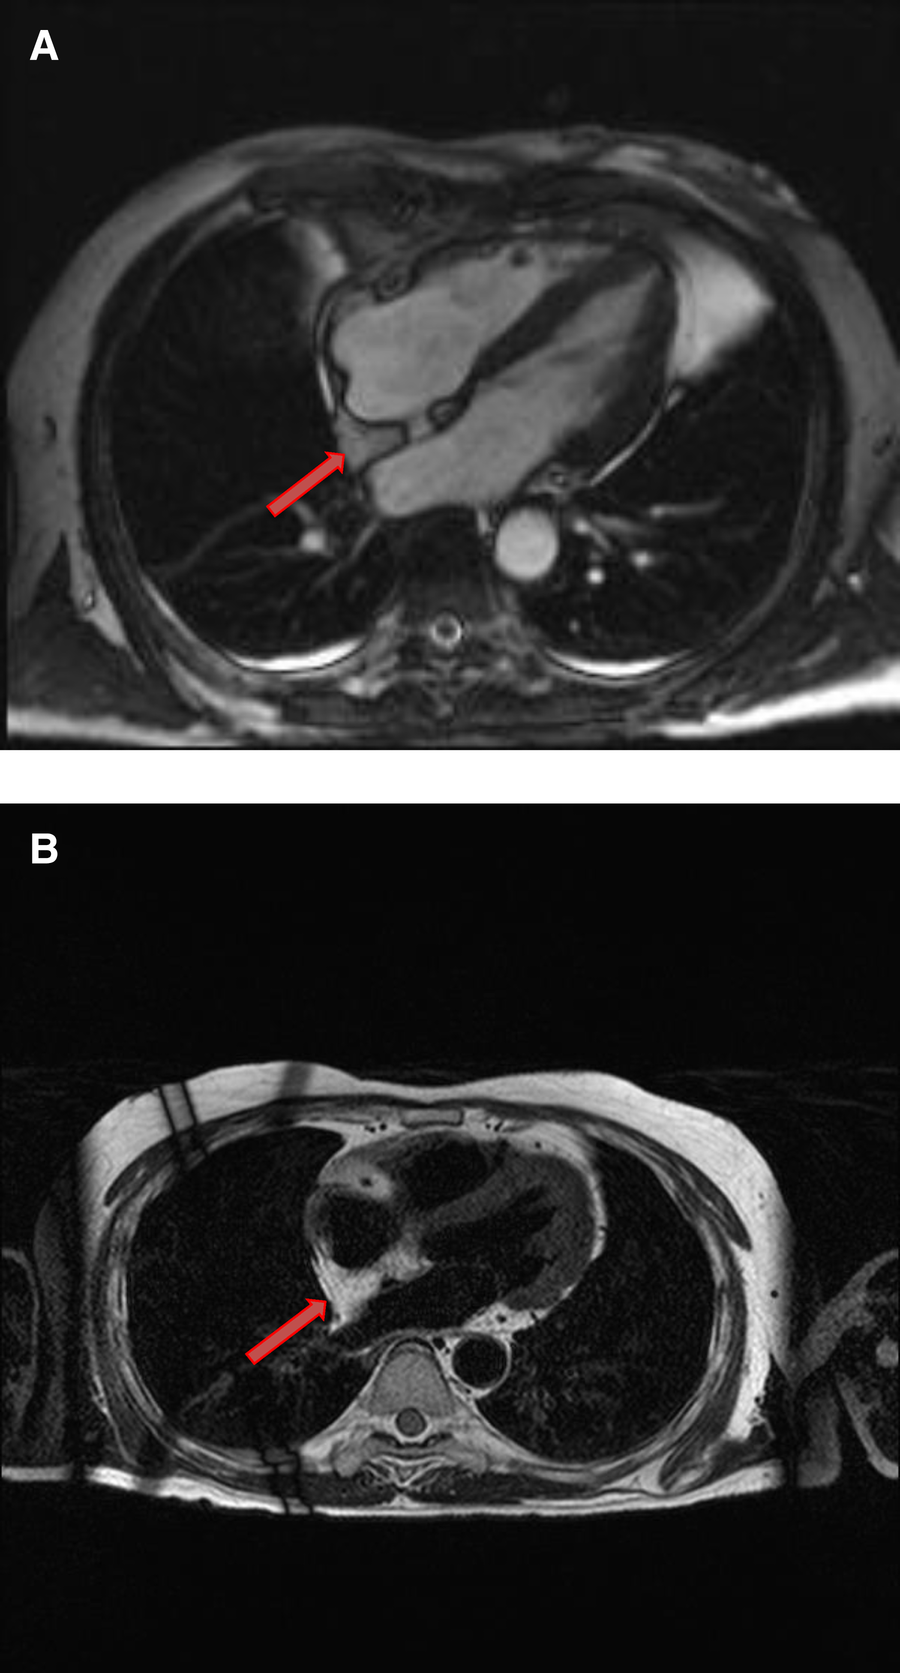

Rhabdomyomas are typically homogeneous in appearance on CMR and are hypointense to the myocardium on SSFP cine sequences. They appear isointense/hypointense on T1 Weighted images and slightly hyperintense on T2-weighted images (Figure 10). On LGE images, they usually show very minimal or no enhancement after the injection of contrast material (Table 1).

Figure 10

A 31-year-old male with left ventricular fibroma. (A) This mass demonstrates no perfusion on first-pass imaging (red arrow, short axis view). (B–F) Homogeneous intense enhancement of the mass is noted on late gadolinium enhanced images (red arrows, 3chamber and short axis views).

4.5.1. Cardiac MRI features

Fibromas are of variable signal intensity on SSFP cine images. As compared to the myocardium, they are usually isointense on T1-weighted images and are characteristically hypointense on T2-weighted images (50). Although, they are generally homogeneous in appearance, a patchy, central hypo intensity may be seen due to central calcification, which gives them a heterogeneous appearance.

They are avascular in nature and do not show contrast enhancement during perfusion imaging. Characteristically, they show intense hyper-enhancement on LGE images. The potential explanation of this intense LGE pattern is that microscopically they are composed of collagen and fibroblasts; therefore, they have a very large extracellular space content. Gadolinium diffuses into interstitial spaces and results in a delayed and persistent concentration of gadolinium contrast agent (Table 1 and Figure 10).